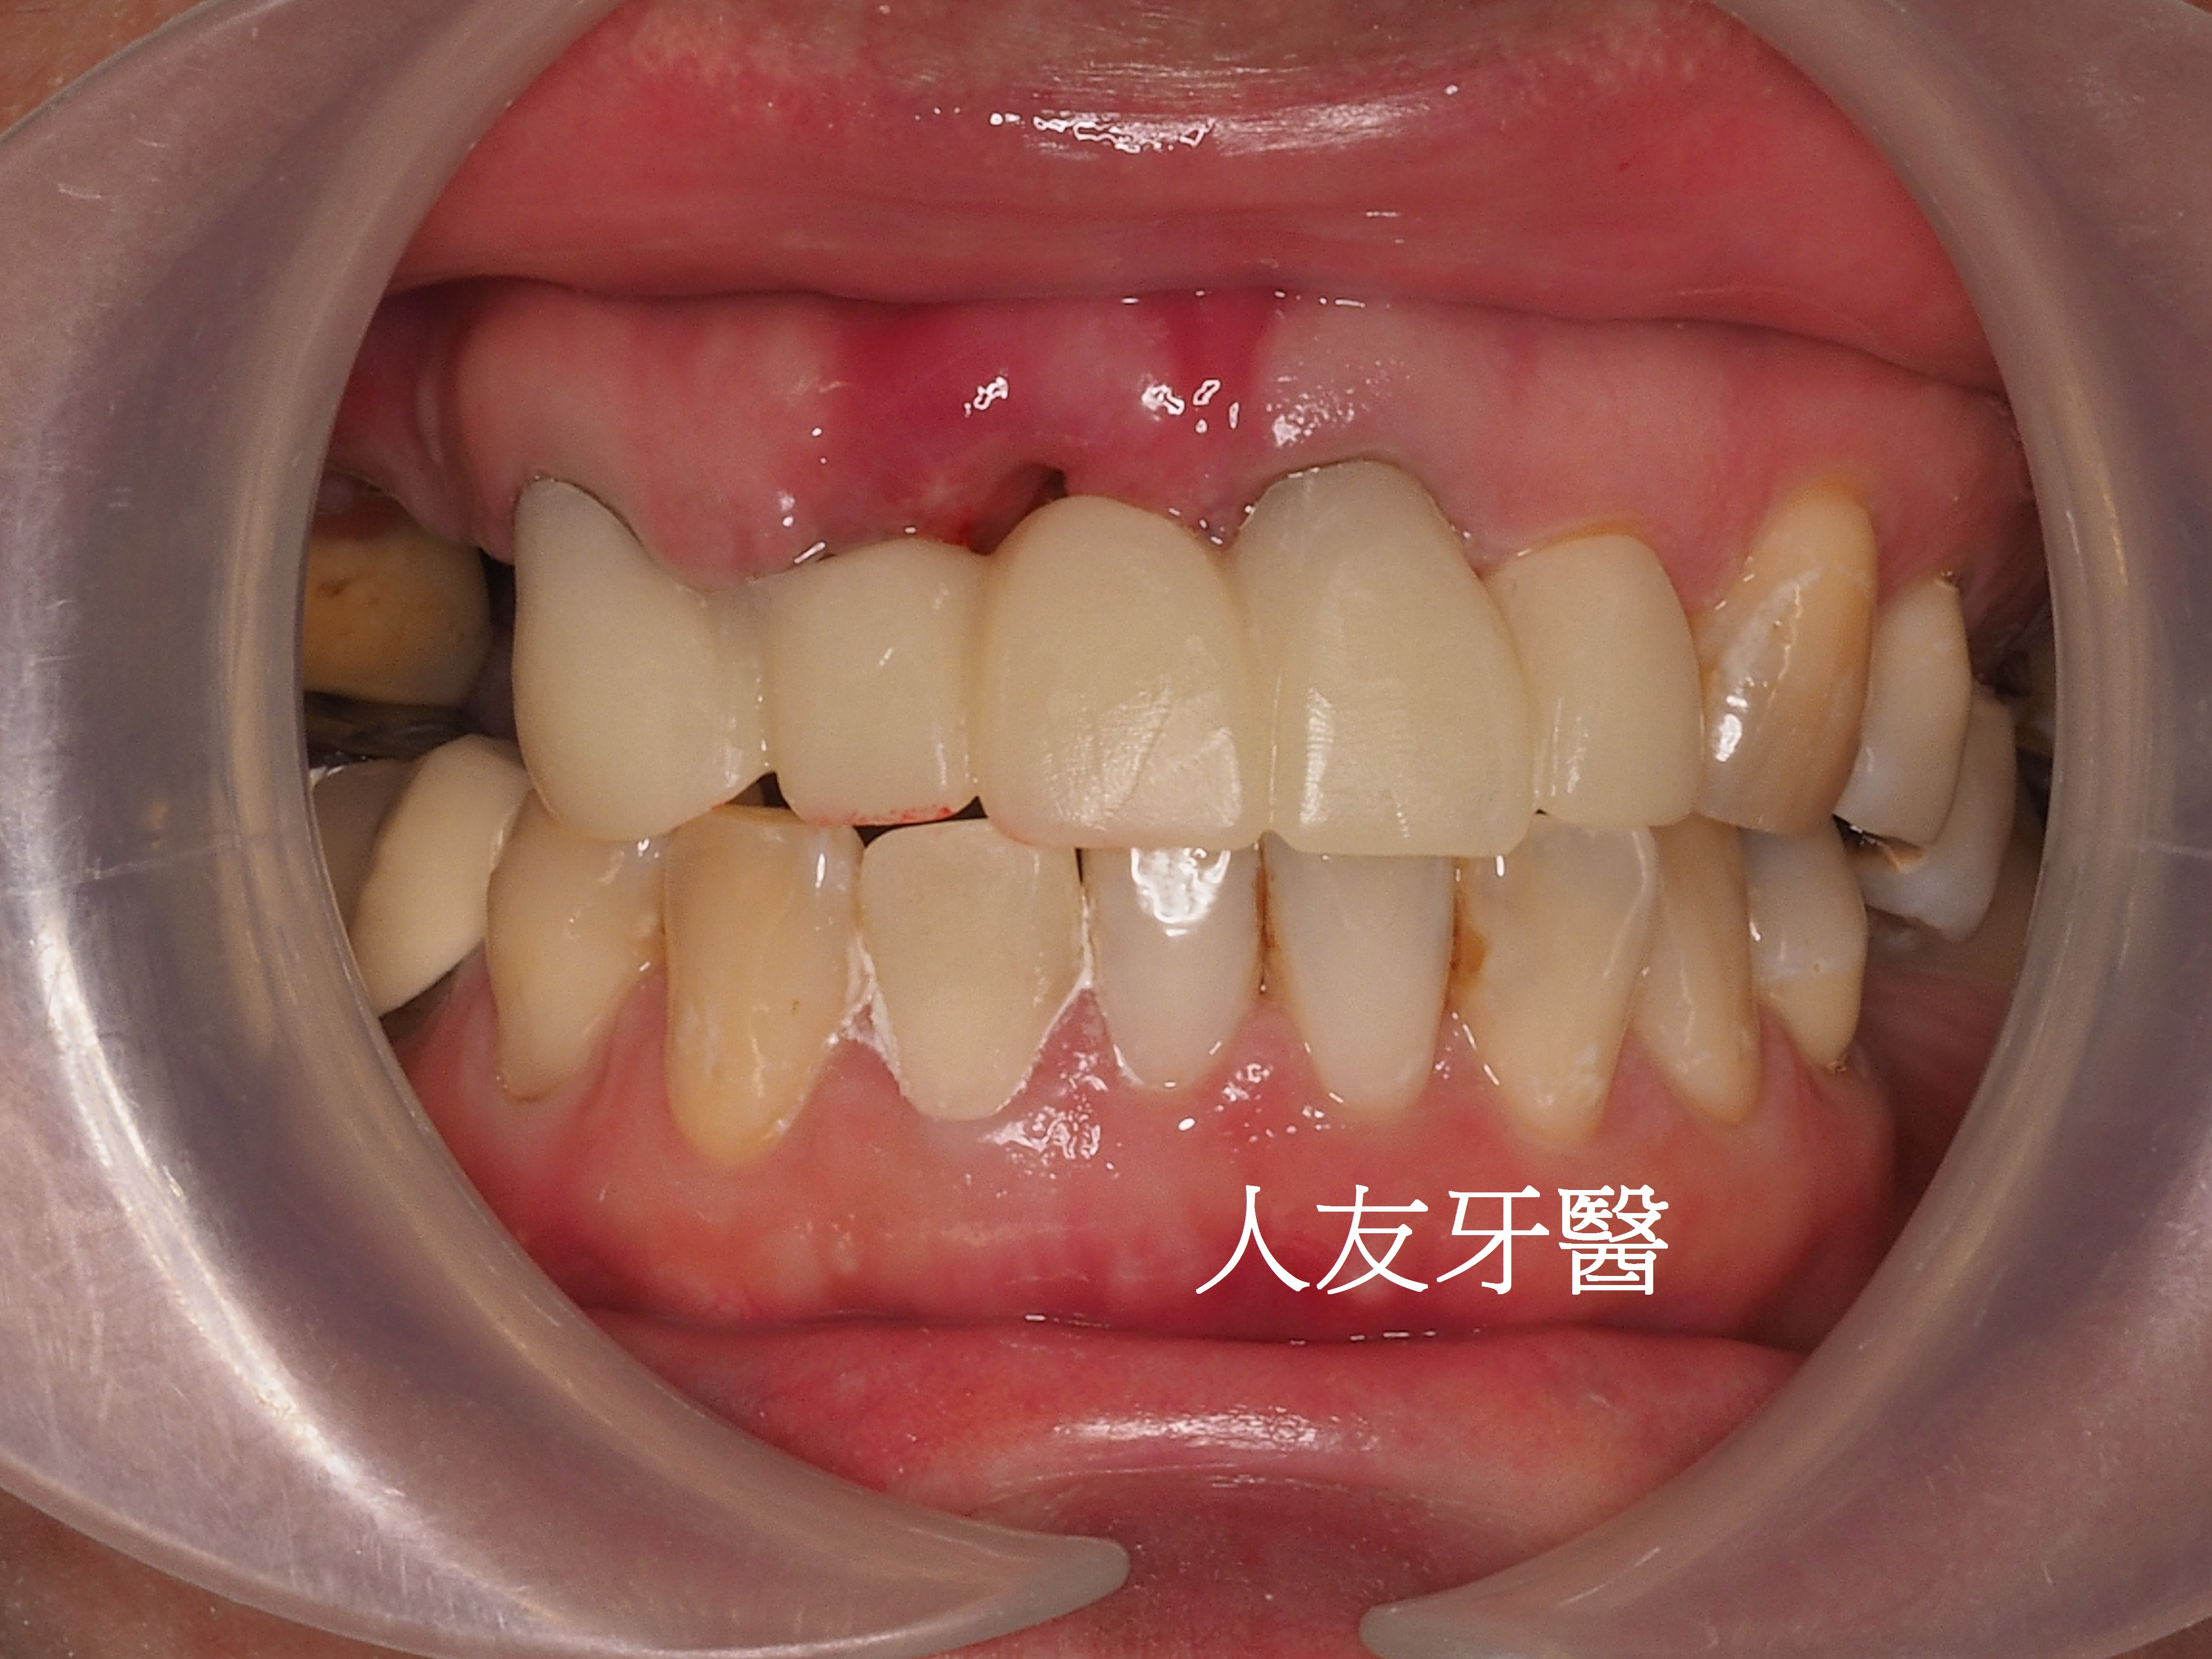

再用左邊側門牙牙套搭橋到右邊正門牙牙套(三顆相連),右邊側門牙獨立做牙套。使門面變好看,說話也不會漏風。

植牙完成後有幫牙套做牙肉色,牙齒才不會看起來太長。患者也不再抗拒看牙齒,說話口齒也很清晰。門面美觀又自然。